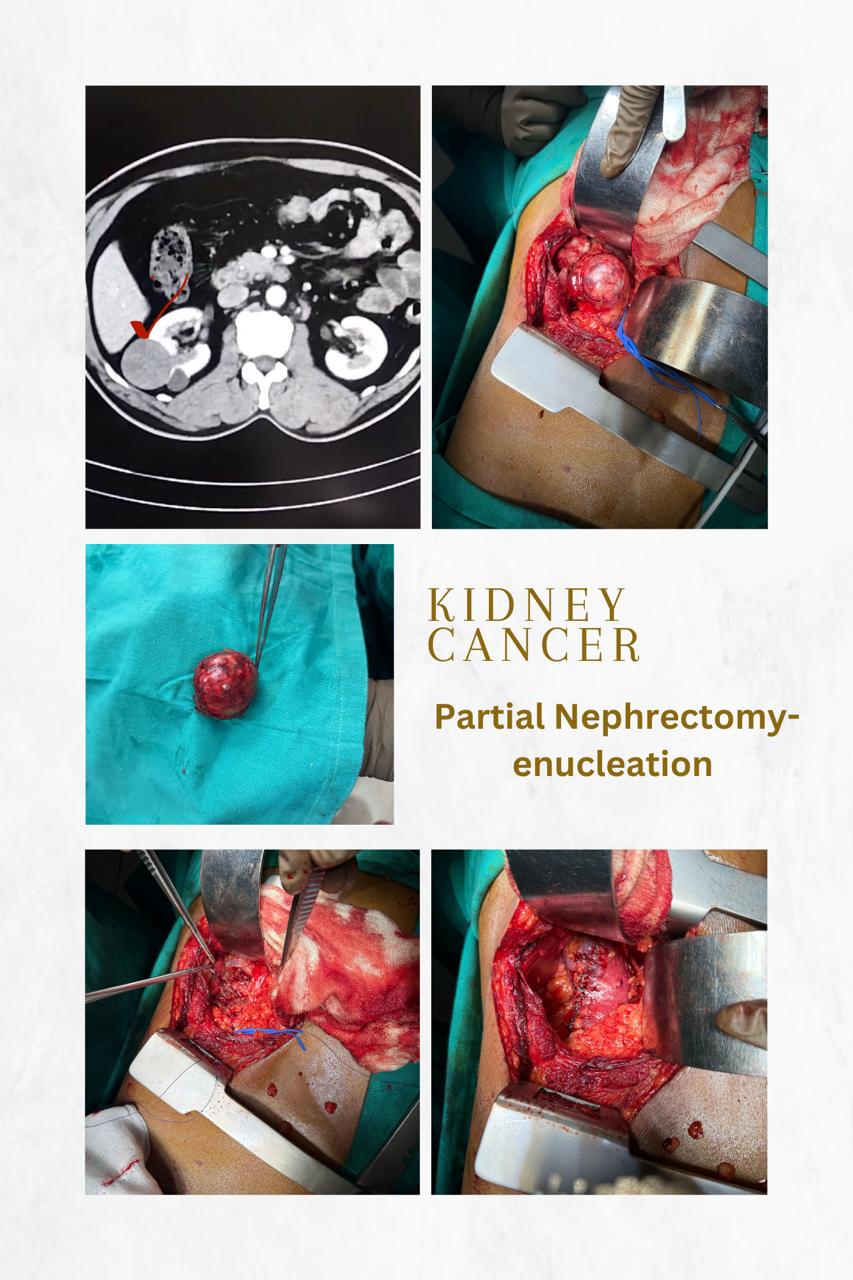

Urological Cancer Treatment

At Jibhakate Urocare Centre in Nagpur, Maharashtra, we specialize in providing comprehensive and advanced urological cancer treatments under the expertise of Dr. Nikhilesh Jibhakate..

Laparoscopic Urological Surgeries

At Jibhakate Urocare Centre in Nagpur, Maharashtra, we specialize in providing advanced laparoscopic urological surgeries for a wide range of urological conditions. Dr. Nikhilesh Jibhakate..

Our Gallery